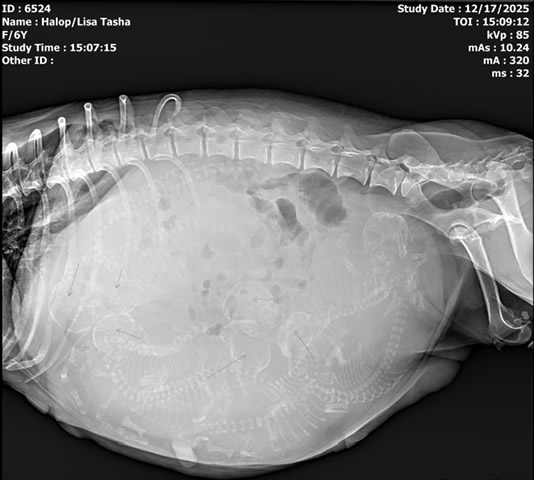

Tasha was very kind to me and decided to have her litter during the DAYTIME, on a WEEKDAY! Seven puppies and we were done! Four boys and three girls; all tri-colored and all huge and thriving. Tasha is tired but as always a great mom and is taking wonderful care of her babies. The ultrasound pic shows one pup and it's beating heart in Nov, and looking at the x-ray, can you make out the babies in her abdomen before they were born? We count skulls and spines - that's how I know how many to expect.